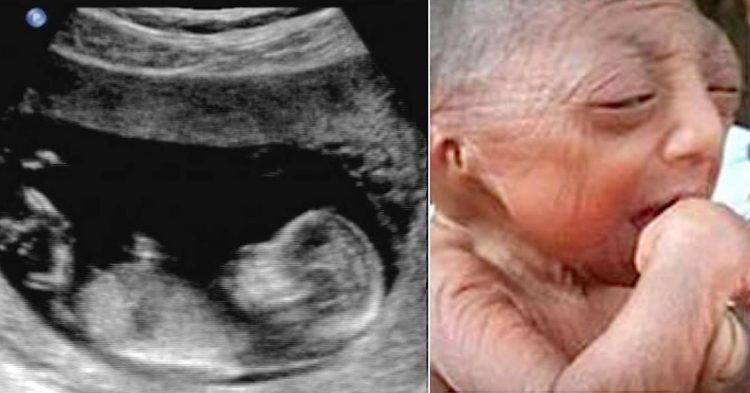

web log free Teen Delivers Baby With Rare Condition. Wait Until You See What He Looks Like Today - Breaking NEWS